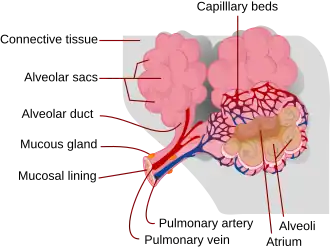

Respiratory zone

The conducting zone of the respiratory tract ends at the terminal bronchioles when they branch into the respiratory bronchioles. This marks the beginning of the terminal respiratory unit called the acinus which includes the respiratory bronchioles, the alveolar ducts, alveolar sacs, and alveoli.[27] An acinus measures up to 10 mm in diameter.[28] A primary pulmonary lobule is the part of the lung distal to the respiratory bronchiole.[29] Thus, it includes the alveolar ducts, sacs, and alveoli but not the respiratory bronchioles.[30]

The unit described as the secondary pulmonary lobule is the lobule most referred to as the pulmonary lobule or respiratory lobule.[25]: 489 [31] This lobule is a discrete unit that is the smallest component of the lung that can be seen without aid.[29] The secondary pulmonary lobule is likely to be made up of between 30 and 50 primary lobules.[30] The lobule is supplied by a terminal bronchiole that branches into respiratory bronchioles. The respiratory bronchioles supply the alveoli in each acinus and is accompanied by a pulmonary artery branch. Each lobule is enclosed by an interlobular septum. Each acinus is incompletely separated by an intralobular septum.[28]

The respiratory bronchiole gives rise to the alveolar ducts that lead to the alveolar sacs, which contain two or more alveoli.[20] The walls of the alveoli are extremely thin allowing a fast rate of diffusion. The alveoli have interconnecting small air passages in their walls known as the pores of Kohn.[20]

The lungs as main part of respiratory tract

The lower respiratory tract is part of the respiratory system, and consists of the trachea and the structures below this including the lungs.[32] The trachea receives air from the pharynx and travels down to a place where it splits (the carina) into a right and left primary bronchus. These supply air to the right and left lungs, splitting progressively into the secondary and tertiary bronchi for the lobes of the lungs, and into smaller and smaller bronchioles until they become the respiratory bronchioles. These in turn supply air through alveolar ducts into the alveoli, where the exchange of gases take place.[32] Oxygen breathed in, diffuses through the walls of the alveoli into the enveloping capillaries and into the circulation,[20] and carbon dioxide diffuses from the blood into the lungs to be breathed out.